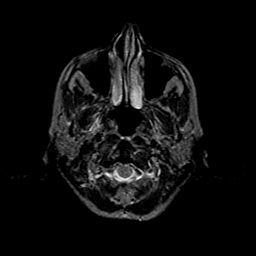

Metastatic bronchogenic carcinoma: T2-weighted MR -- Slice #0

[Home][Help][Clinical] Slice 0